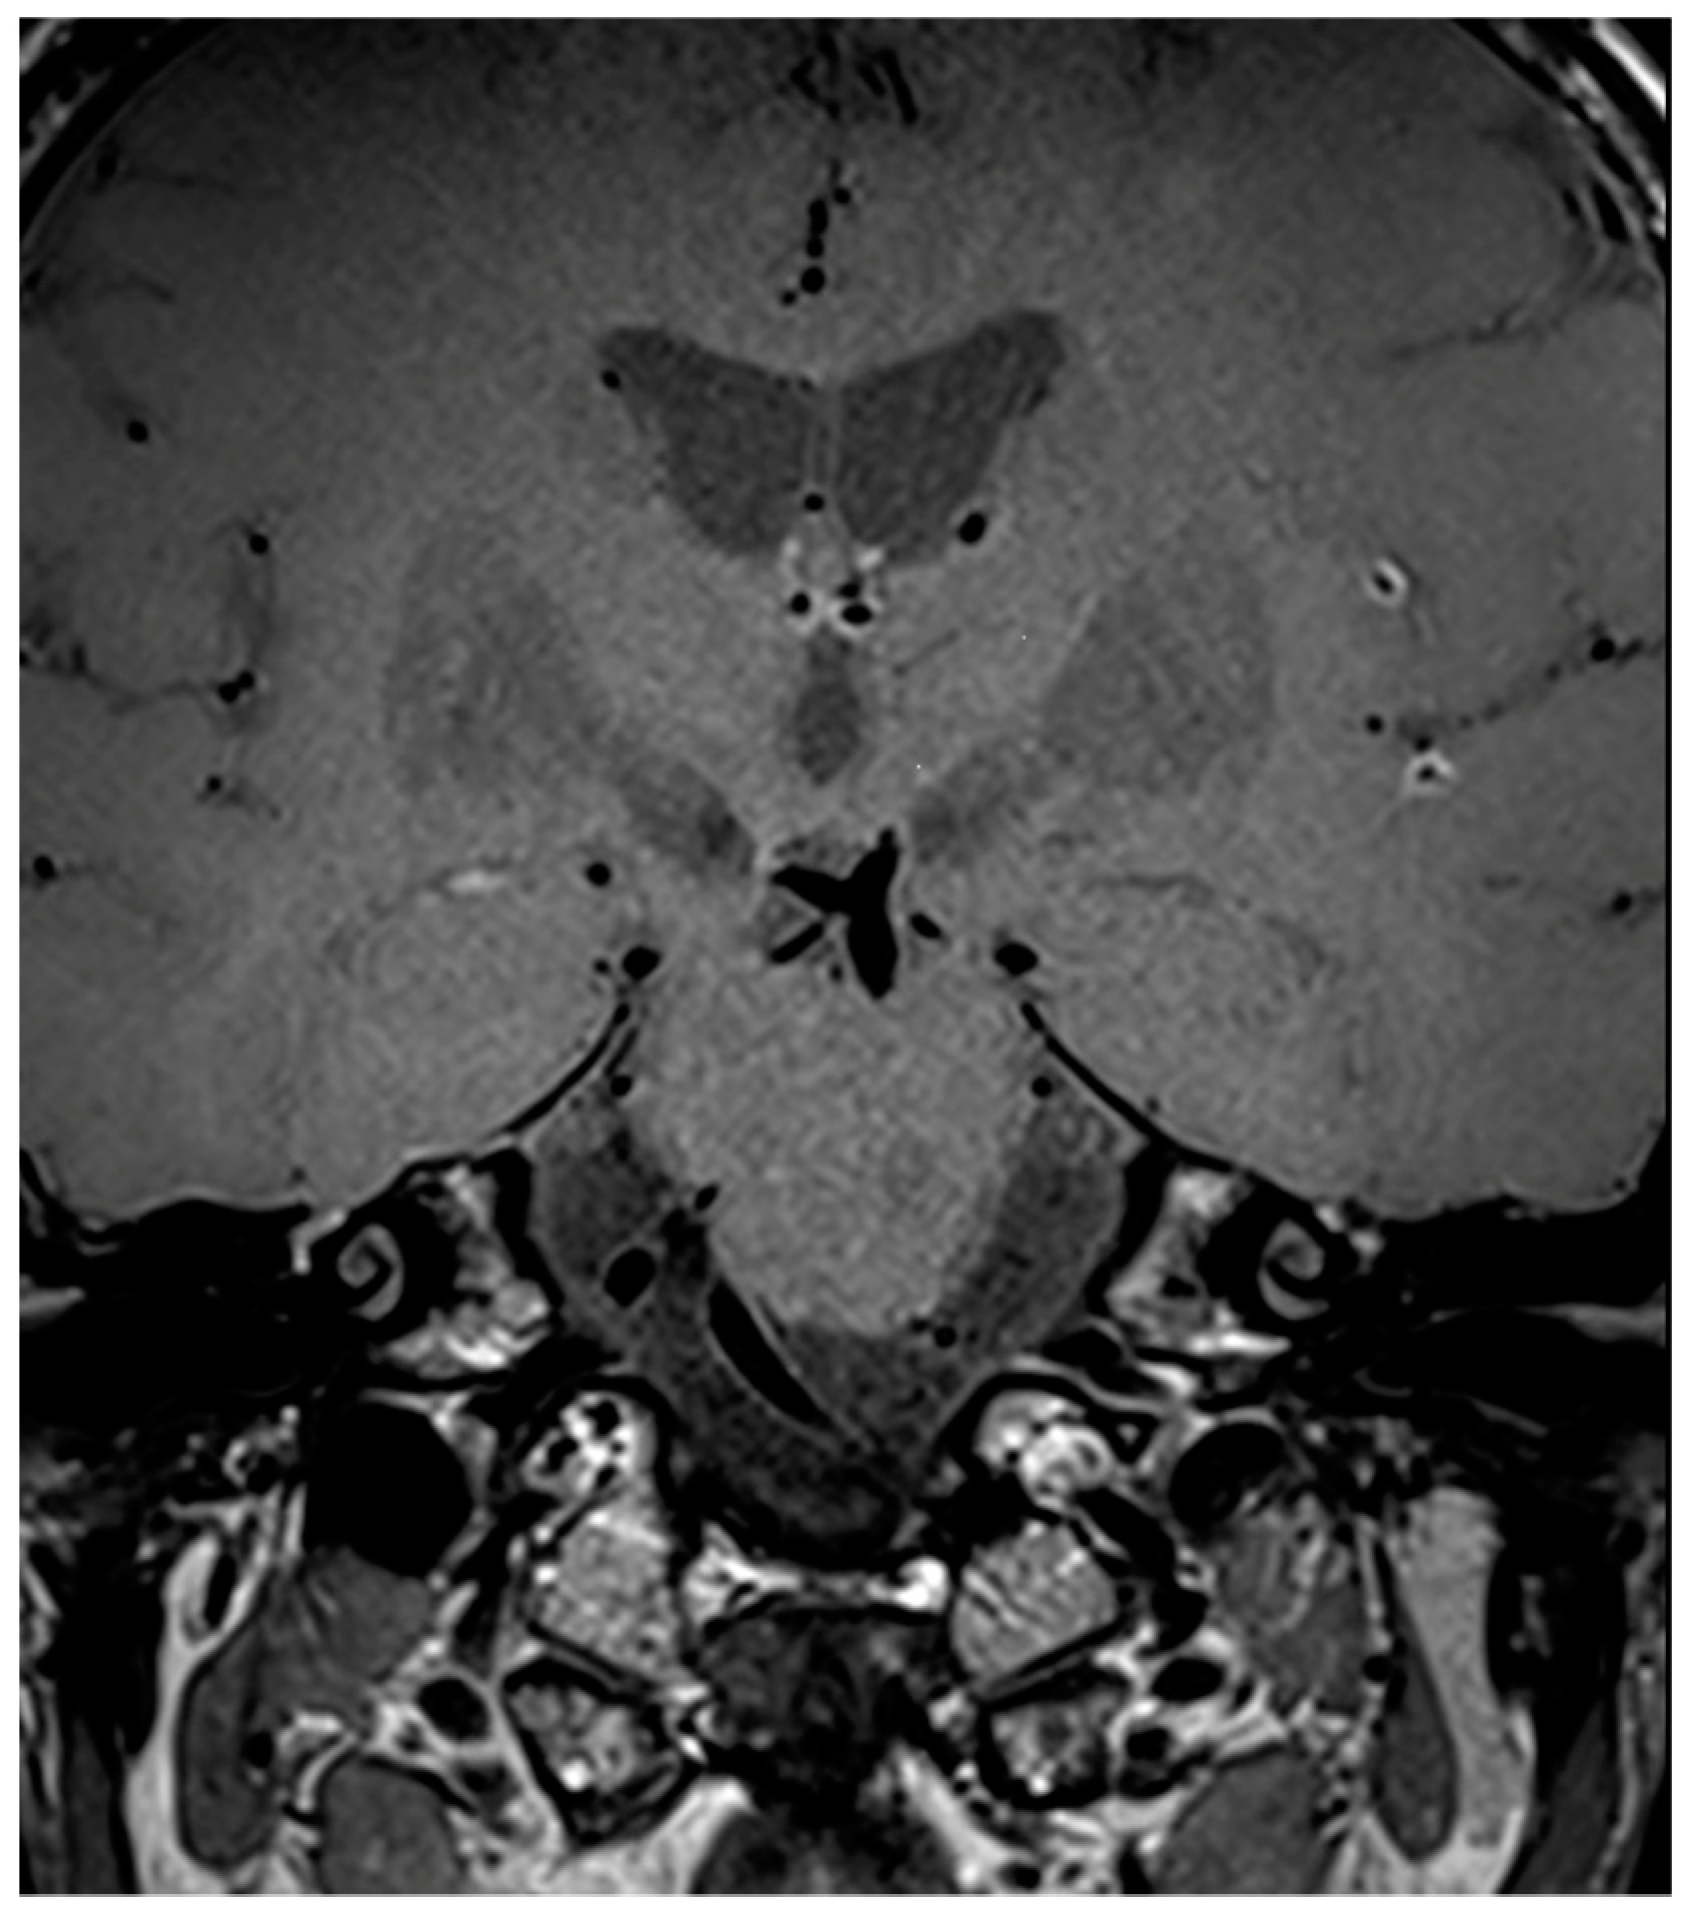

7. Legend